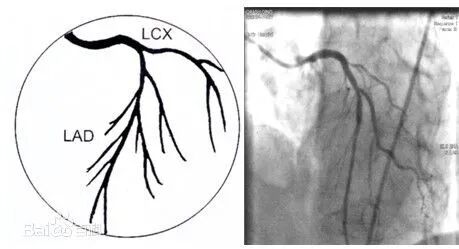

➤左冠状动脉主干(LM)起源于升主动脉左后方的左冠窦,行至前室间沟时分为左前降支(LAD)和左回旋支(LCX)。

✓前降支通常供应部分左室、右室前壁及室间隔前2/3的血液,其分支分别向三个方向发出,即对角支(D)、右室前支、室间隔支。